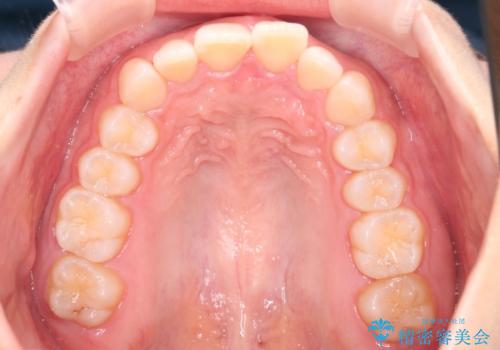

- 上の前歯の出っ歯と前歯の深い咬み合わせを治したいとのことで来院された患者様です。

上顎の歯は後方移動とIPR(歯と歯の間を削る)によって口元が引っ込むように、下顎は歯列全体の拡大とIPRによって上顎とバランスよく咬み合うように設計し、インビザラインにより治療を行うこととしました。

上顎歯列の後方への移動量が多く、右側の奥歯の咬み合わせを改善する必要もあったため、治療には長期間を要しました。